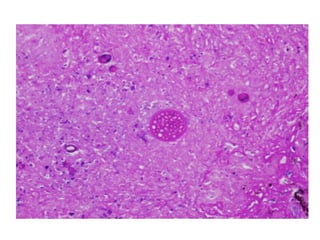

• #34 Cryptococci in perivascular space

• #35 Mucicarmine

• #36 Alcian Blue

• #37 PAS

• #38 Mucicrmine stain

• #39 CNS